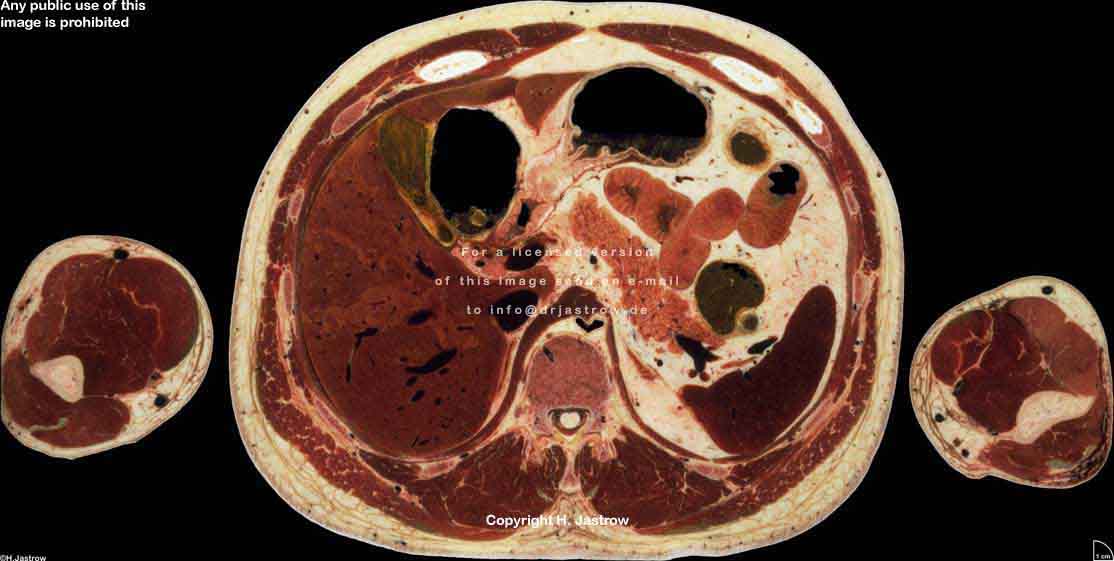

Visible Human male: Sectio transversalis 1557

CT

NMR

Pd                          / T2 \                         T1